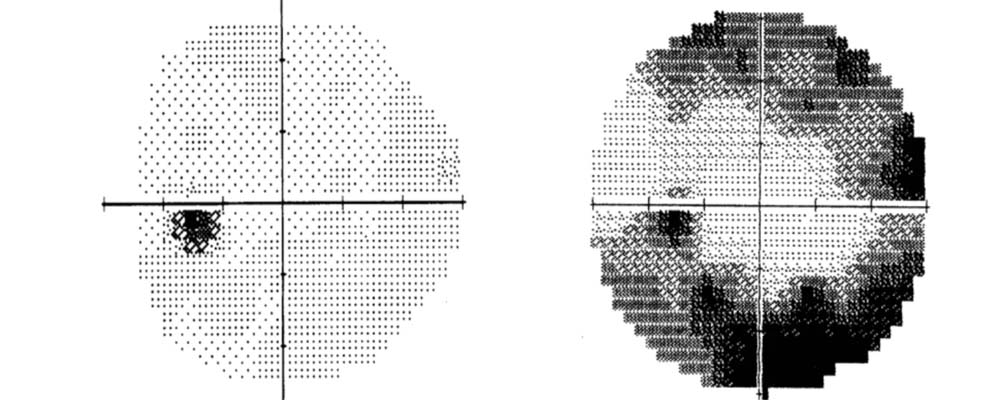

Champ visuel